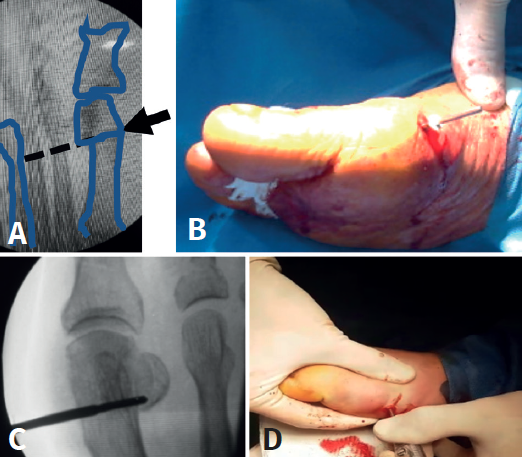

Mediante abordaje de 5 mm a nivel plantar proximal al bunion se realiza capsulotomía y exostectomía (Figuras 1A, B y C). Por otro abordaje de 3 mm realizado a 5 mm dorsal y distal del primero y a 15 o 20 mm proximal a la superficie articular (entre 7 y 10 mm del centro geométrico de la cabeza), extraarticular y equidistante a la cortical dorsal y plantar, se procede al tallado de la osteotomía de Chevron con fresa Isham larga (2,0 × 12 × 65 mm), (Figura 1D). Con la fresa dirigida, preferentemente, perpendicular al cuarto metatarsiano y llevándola ligeramente a plantar o dorsal según quisiéramos descender o elevar, respectivamente, la cabeza metatarsiana, perforamos el primer metatarsiano. En modelos sin fijación, elegimos esta dirección hacia proximal para lograr un leve acortamiento, que relaja la articulación metatarsofalángica y reduce las posibilidades de pérdida de corrección de la cabeza (Figura 2). En modelos con fijación se dirige más hacia distal, con referencia en la diáfisis del segundo metatarsiano o incluso perpendicular al primer rayo. Realizamos el corte dorsal casi vertical y el corte plantar lo más horizontal posible (paralelo al suelo), con dirección de distal a proximal, tratando de que esta rama sea más larga que la anterior. Se puede lograr de forma adicional corrección del DMAA. Una vez completa la osteotomía, se desplaza a lateral manualmente bajo visión radioscópica hasta que se logra una posición satisfactoria. No se coloca osteosíntesis. Se procede a la adición de otros gestos percutáneos de ser necesarios (liberación lateral de partes blandas, osteotomía de Akin, osteotomías de metatarsianos o dedos menores) (Figura 3).